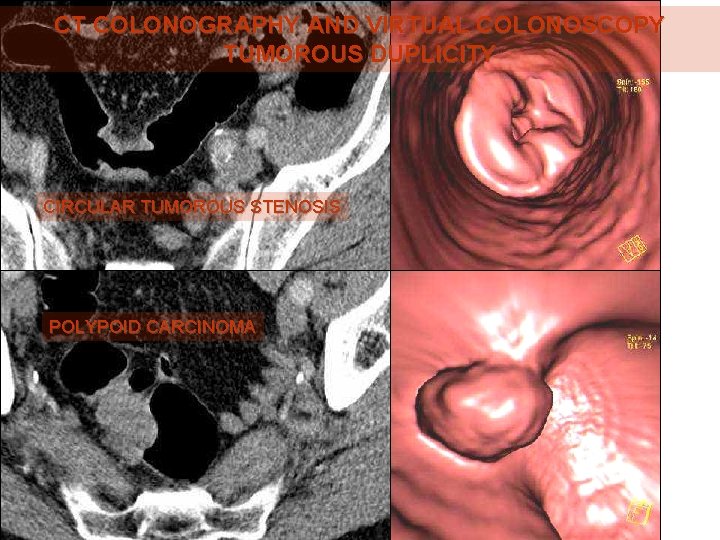

CT COLONOGRAPHY AND VIRTUAL COLONOSCOPY TUMOROUS DUPLICITY CIRCULAR TUMOROUS STENOSIS POLYPOID CARCINOMA